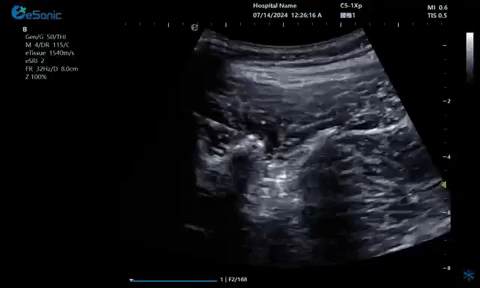

超声引导下神经根阻滞,也可以

做腰神经后支